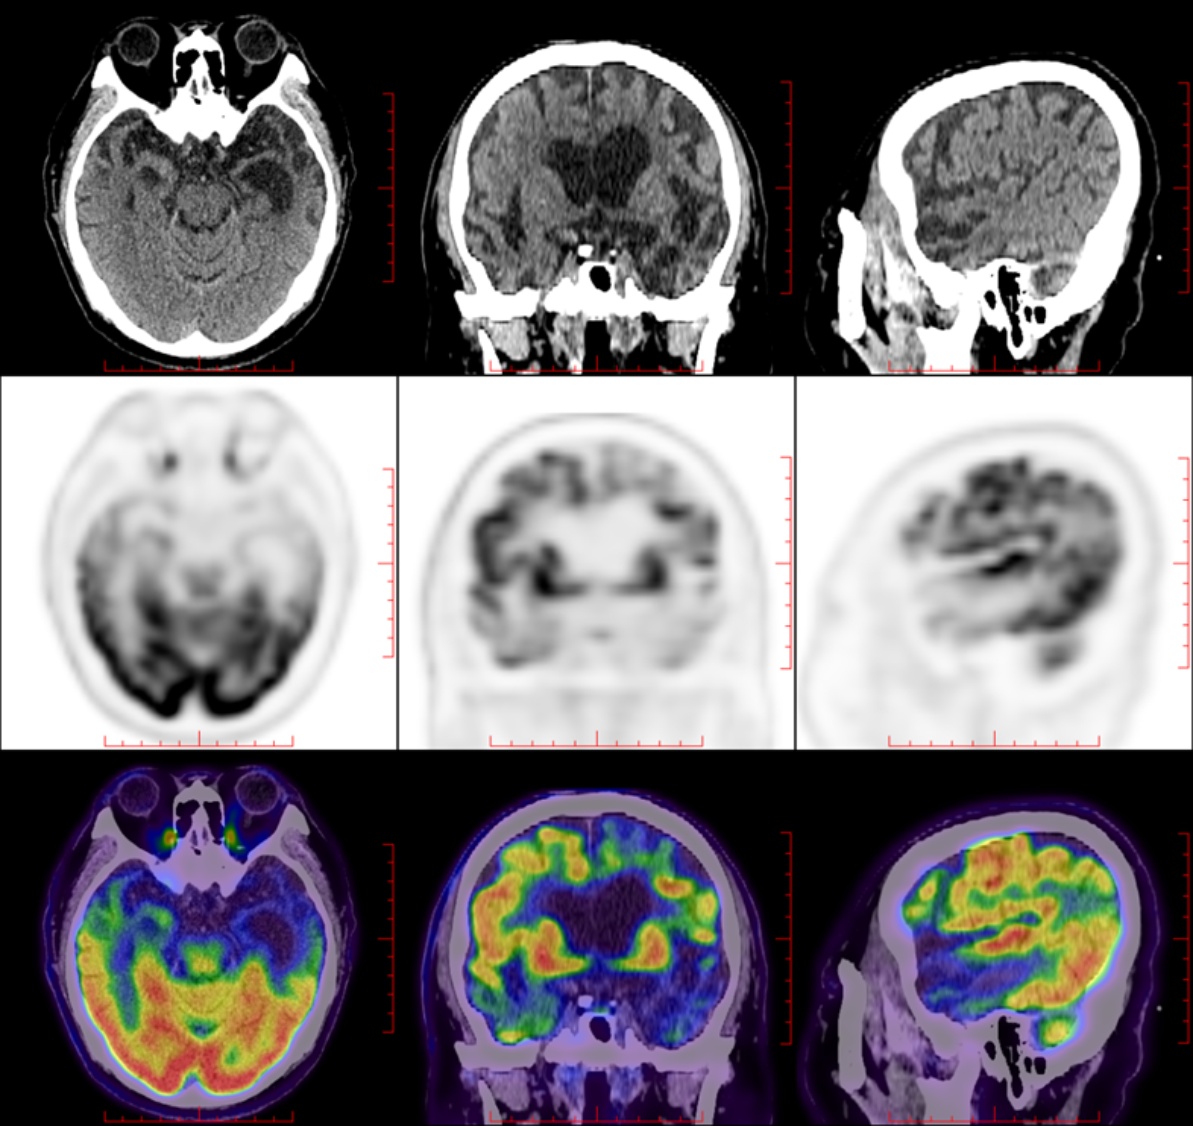

PET-CT:大脑皮质β淀粉样蛋白(Aβ)未见明显沉积;双侧大脑半球多发皮质代谢减低,以左侧额颞叶为著;符合额颞叶痴呆影像学表现(图3图4)。

Figure 3. The cerebral cortex shows negative Aβ deposition

3. 大脑皮层Aβ沉积阴性

自主神经功能的中枢调控网络主要包括岛叶、前扣带回、眼眶额叶皮层、杏仁核、下丘脑等脑区,它们协调内脏感觉信号、调节血压、心率及代谢等自主神经功能[8]。额颞叶、岛叶等是bvFTD的主要病理累及部位,病理改变是tau蛋白或TDP-43蛋白异常蓄积所致,造成神经元丢失、突触功能障碍而影响自主神经各功能调控通路,造成血压、心率调节异常,引起体位性低血压、晕厥等症状[8] [9]。本例患者PET-CT明确显示双侧额颞叶、岛叶及前扣带回葡萄糖代谢显著减低,与自主神经中枢调控网络的关键脑区高度吻合:岛叶代谢减低直接导致内脏感觉信号整合障碍,使患者无法及时感知体位变化后的血压波动;前扣带回代谢异常破坏了血压调节的自上而下调控通路,无法快速纠正体位性血压下降;额颞叶代谢减低则进一步加剧了后期行为认知症状与自主神经功能的协同损害,形成“感知–调节–行为”的多环节功能障碍链,这一影响与功能解剖的对应关系直接支持该脑区受累的病理机制。